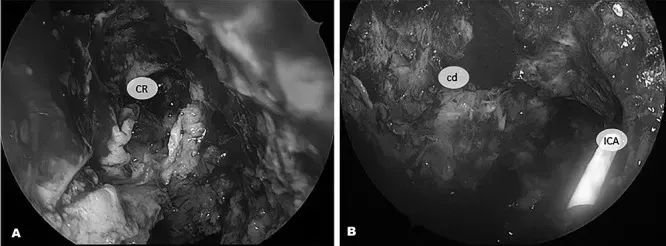

术中操作:经蝶窦入路的内镜下手术视野。A:在制作鼻中隔瓣及反向瓣后,暴露斜坡隐窝(CR)。B:肿瘤切除后,暴露斜坡硬脑膜(cd),通过多普勒检测到岩部颈内动脉(ICA)。

高清鼻内镜如探照灯般照亮深邃的颅底迷宫,神经导航系统构建出三维安全路径,多普勒超声随时预警血管危险,神经电生理监测则像忠诚的卫士守护着每一根重要神经。主刀手持精密器械,以锐性刮匙精准剥离病变骨质,高速磨钻去除周边骨质。面对已被病变浸润的肌肉组织,团队展现了"有所为有所不为"的手术智慧——既确保肿瘤近全切除,又最大限度保护神经功能。

手术最后的艺术在于创面修复:取自脐周的脂肪组织犹如天然填充物,与预先精心设计的鼻中隔复合瓣完美配合,为手术区域披上量身定制的“防护衣”。这场融合了多模态影像导航、经鼻内镜入路和自体组织复合修复三大技术亮点的颅底手术,不仅成功拆除了威胁妮娜生命的“炸弹”,更展现了现代神经外科手术的精湛艺术。